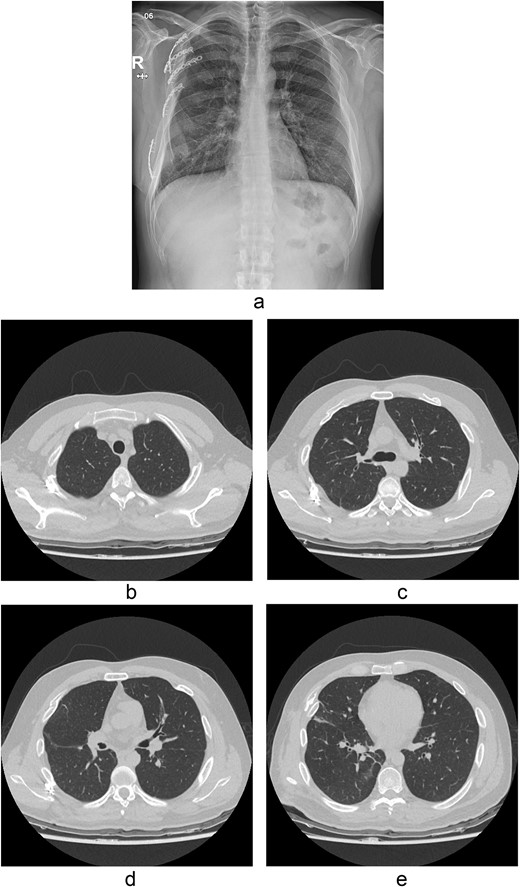

A 31-year-old unconscious male was in an unwitnessed accident when a car hit the motorcycle he was driving. A rescue team transported him to the emergency department. Clinical examination revealed hypoxia with SpO2 at 85%, tachycardia at 126 bpm, hypotension of 69/58 mmHg, and hypothermia at 35.8°C. Initial arterial blood gas analysis (ABGA), pH, PaO2, and pCO2 were 6.92, 49, and 58, respectively. Chest X-ray showed right hemopneumothorax, mediastinal shifting, and multiple bilateral rib fractures (Fig. 1). A right-side closed thoracostomy was performed. The chest drainage of 1 L was bloody. Chest computed tomography (CT) showed fractures in the right ribs 1 to 9 and left ribs 1 to 7, as well as lung contusions, multiple lung lacerations, right hemopneumothorax, and active hemorrhage in the right upper and lower lung lobes (Fig. 2). Brain and abdominopelvic CT showed no organ injury. An emergency thoracotomy was ordered.

A contrast-enhanced chest CT scan after blunt chest trauma. Chest radiograph showed right hemopneumothorax and left hydropneumothorax. Multifocal extensive hemorrhage/pneumatocele formation was visible on the right side along with combined active bleeding (arrows) in the right lung.